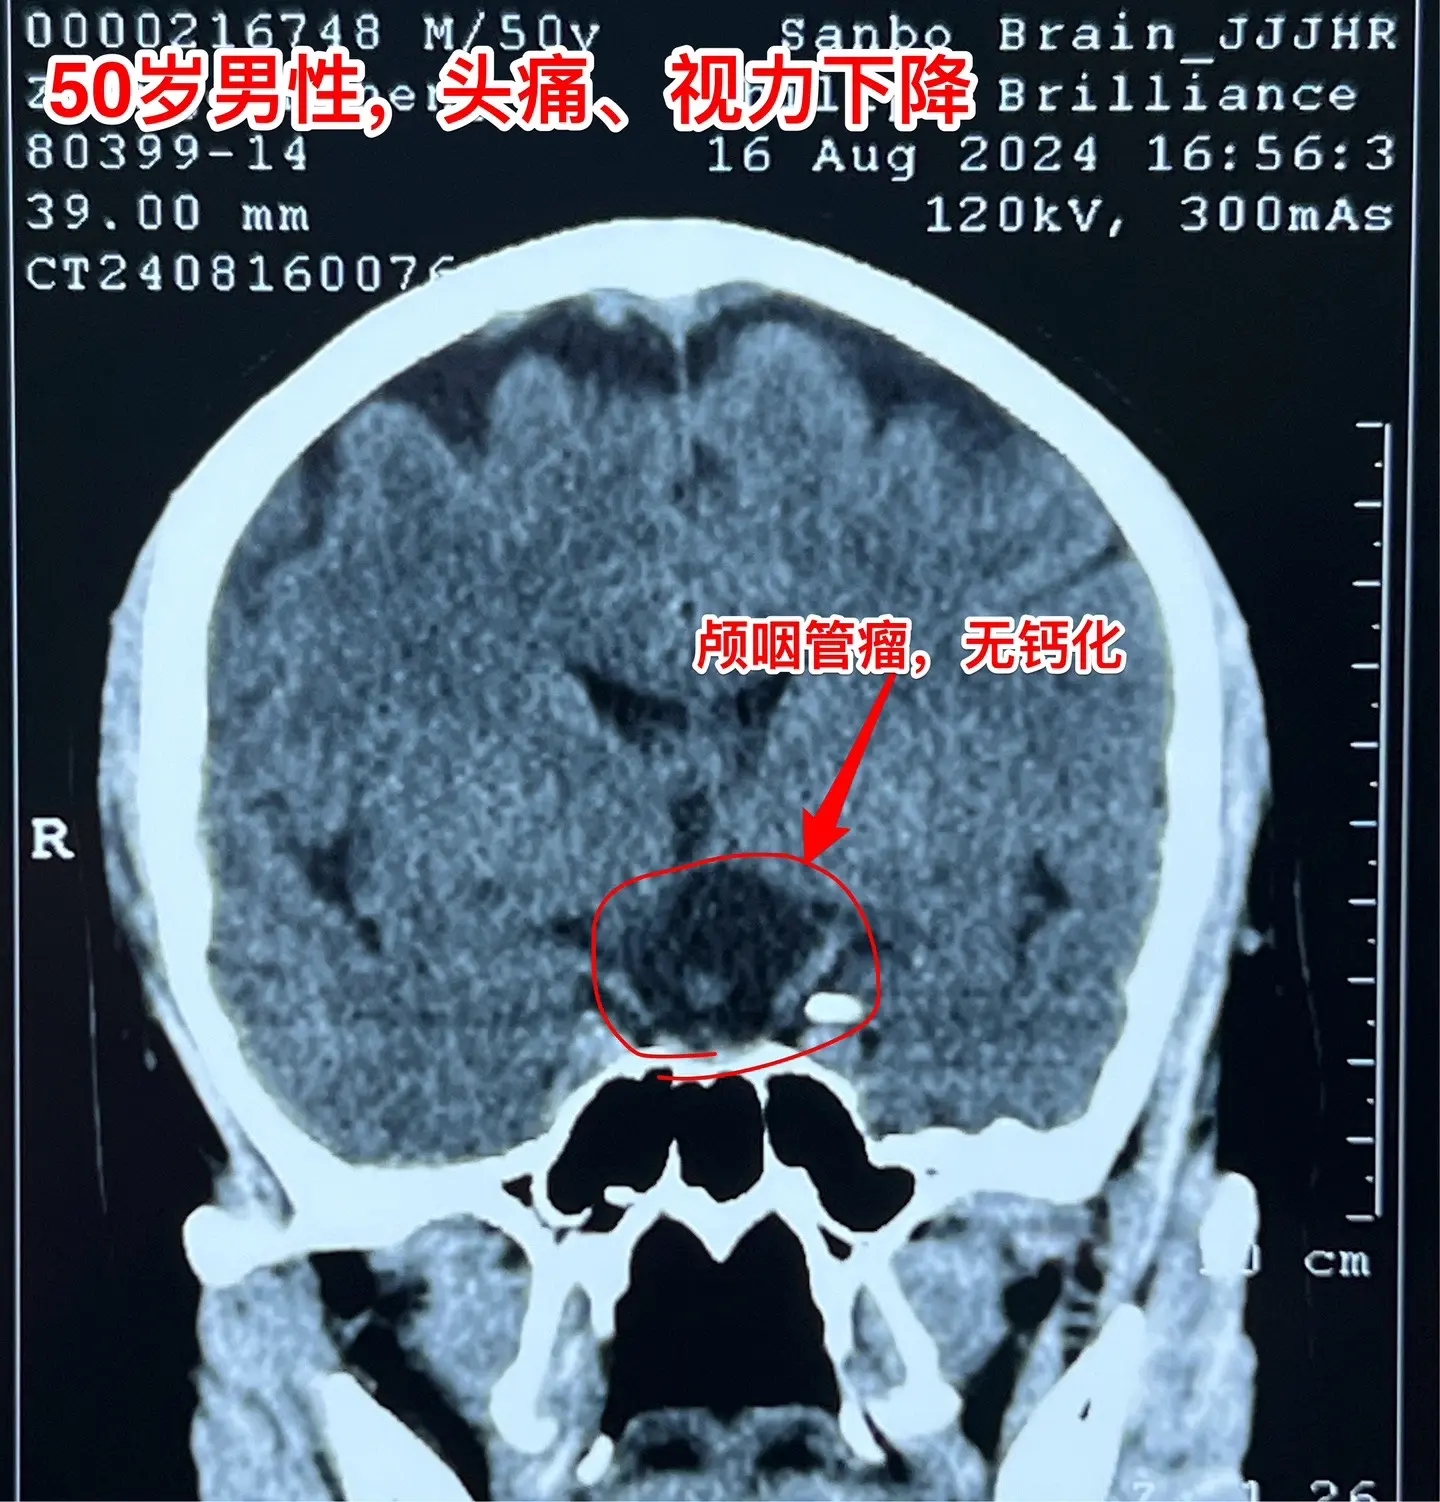

颅咽管瘤手术,出院3天就开车,合适吗?50岁的山东临沂男性,因头痛一年,左眼视力下降三个月于2024.8.16在我科住院。左眼视力0.1,右眼视力1.0。8月22日行开颅手术切除颅咽管瘤,手术后视力改善,身体恢复顺利,9月2日出院了,出院前测左眼视力0.5,右眼1.0。出院时精神好,体力好。 9月8日患者女儿和我联系,说患者出院三天就开车了。我告诉她,需要复查视力和视野,如果视野有缺损,开车是有风险的,不适合开车。